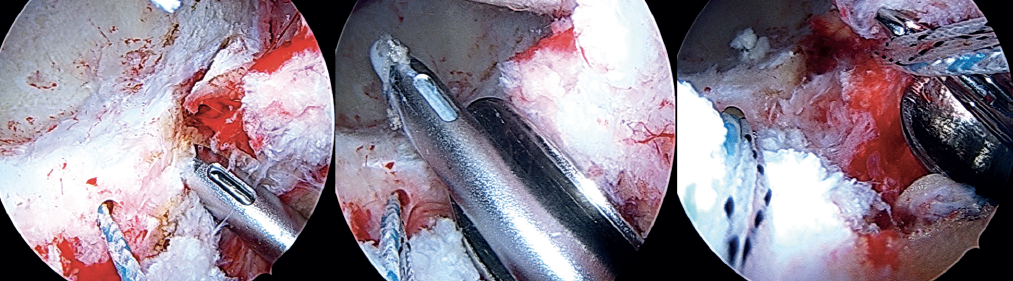

Insertion of the graft

Forceps are inserted from the posterior portal, taking care that they lie posterior to the last anchoring, and from the anterior modified portal we introduce the suture anchored to the anterior portion of the graft, likewise taking care that it lies anterior to the most anterior anchoring. Once within the joint, this suture is grasped with the forceps inserted from the posterior portal, and then traction is exerted posterior until it emerges from the posterolateral portal. Lastly, traction is continued to introduce the graft, making it emerge through the posterolateral portal. At this point, the anchoring preassembled in the graft is guided towards the pre-drilling made and is inserted, thereby fixing the most anterior portion of the graft in the case of using a knotless anchoring or extracting the suture and threading the tendon to then perform a knotted technique(Figure 12). After positioning and fixation of the most anterior portion of the graft, the filaments are passed around the graft in sequence, and are tightened little by little, maintaining traction from the posterolateral portal, and fixing and positioning the entire plasty from anterior to posterior (Figures 13 and 14). Once all these steps have been completed, the excess graft is radiofrequency amputated from the posterolateral portal. Lastly, the hip is evaluated dynamically in all the planes of motion, checking fixation, the position of the graft, and recreation of the sealing effect at the femoral head-neck junction with the acetabular labrum (Figure 15).